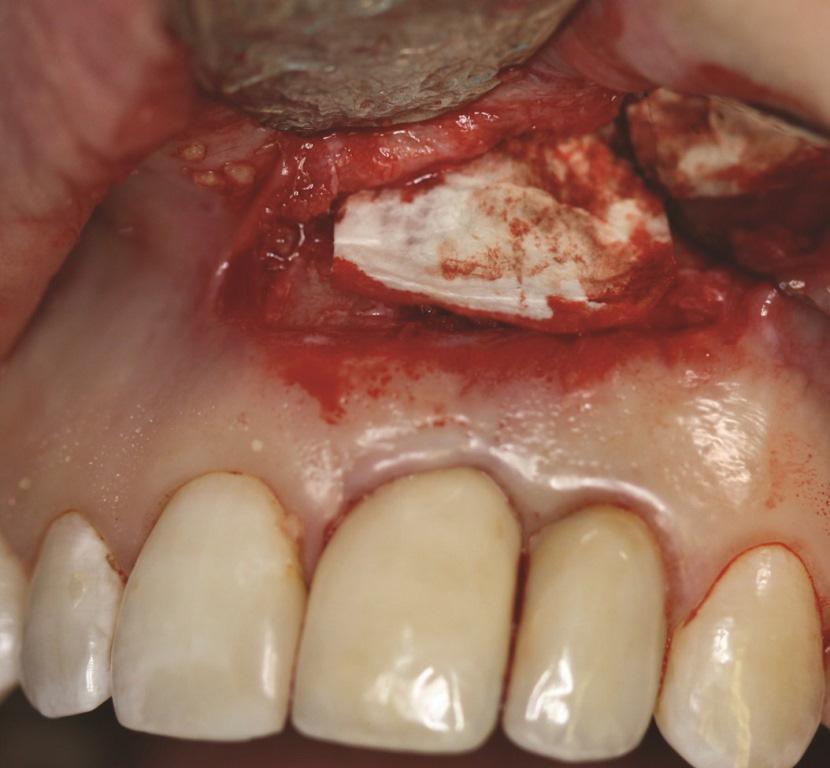

Пациенту в случае 2 был выполнен гребневой разрез с отслаиванием полнослойного лоскута, затем зуб № 1.4 был удален (Фото 9). Кюретаж имплантата проводили по тому же протоколу, что и в случае 1. ЛКА был смешан с небольшим количеством доксициклина и помещен вокруг имплантата (Фото 10). Рассасывающаяся коллагеновая мембрана (не показана) была зафиксирована с помощью пина. Первичное закрытие было достигнуто с использованием швов из расширенного политетрафторэтилена (РПТФЭ) (Фото 11). Немедленный послеоперационный рентгеновский снимок показал костное наполнение и пин (Фото 12).

Фото 9. Случай 2: Отслоение полнотолщинного лоскута, удаление зуба № 1.4, кюретаж и очистка имплантата № 1.3 титановыми скейлерами и титановой щеткой с суспензией доксициклина с физиологическим раствором. Обратите внимание на обширное обнажение резьбы имплантата, приближающееся к верхушке. Подвижности имплантата не отмечалось.